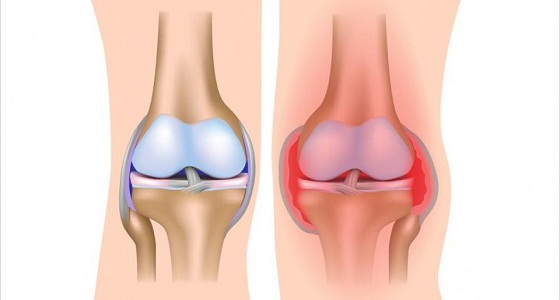

أهم 4 نصائح للوقاية من التهاب المفاصل